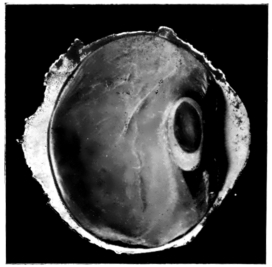

PLATE II.

FACING

PAGE

10.

LENS DISLOCATED BETWEEN CILIARY BODY AND SCLERA

curly bracket span

38

11.

NUCLEUS OF CATARACT FREELY MOVABLE BETWEEN THE AQUEOUS AND VITREOUS CHAMBERS

12.

LENS IMPACTED IN ANGLE OF ANTERIOR CHAMBER

13.

CAPSULE OF MORGAGNIAN CATARACT IMPACTED IN ANGLE OF ANTERIOR CHAMBER

14.

LENS FLOATING FREE IN VITREOUS CHAMBER

15.

LENS LIGHTLY IMPRISONED IN EXUDATE INTO VITREOUS CAVITY